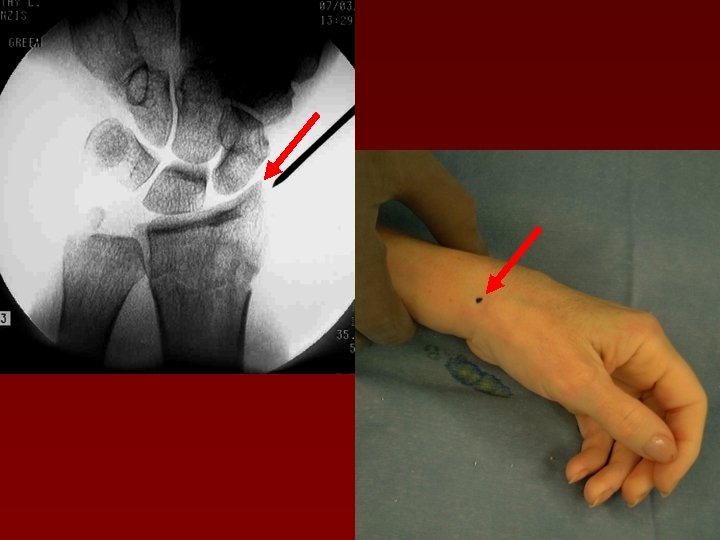

Определение точек введения спиц

Углы, под которыми вводятся спицы в 2 -х проекциях

КЛЮЧЕВЫЕ МОМЕНТЫ • Сначала - репозиция • Используйте спицы Киршнера 1, 6 мм • 3 спицы проходят через 2 кортикальных слоя • Тест удаления спиц (“PINCH” TEST) • Наличие ЭОПа